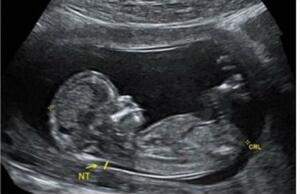

The estimated date of delivery "EDD" or when the pregnancy is considered fully termed is a major concept. Each pregnant woman would definitely want to know how far in pregnancy she is and when is her estimated delivery could be. This webinar is meant to let you know how the earliest ultrasound scan gives the most accurate answers to such questions and for most importantly will let you know when to go by the estimated DATE calculated by ultrasound rather than by the one given based on her LMP.